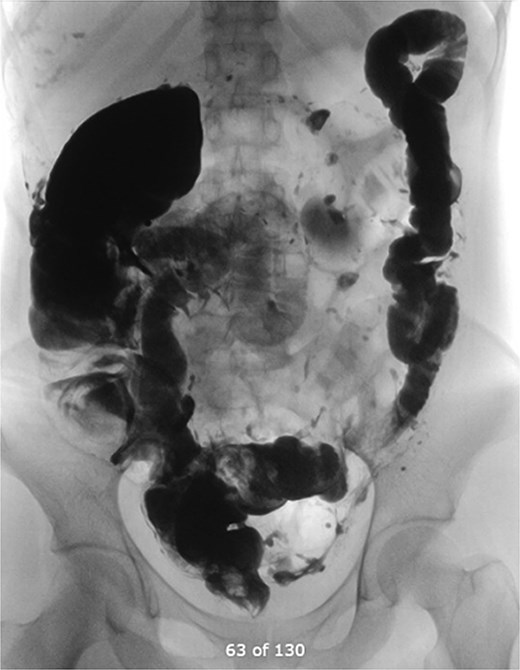

Six weeks later, a distal loopogram was performed using water-soluble gastrogafin contrast, which demonstrated free flow of contrast with no evidence of strictures or leakage (Fig. 7). The patient successfully underwent reversal of ileostomy 2 months afterward and recovered uneventfully.